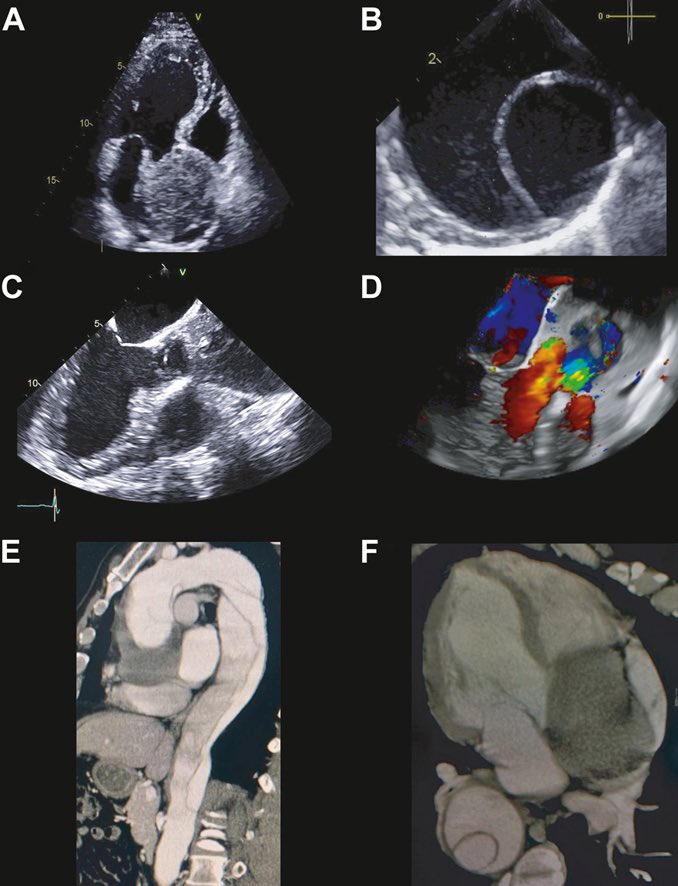

Felicitamos a la Dra @laubaquerob , Dra Loaisiga y Dr Alvarado Sánchez por la publicación de este caso! Excelente trabajo en equipo!

Excited to share my first publication in JACC! Presenting a clinical vignette featuring a patient with Stanford type A chronic dissection. Thanks to comprehensive multimodal imaging, a successful operation two years later was achieved without complications.